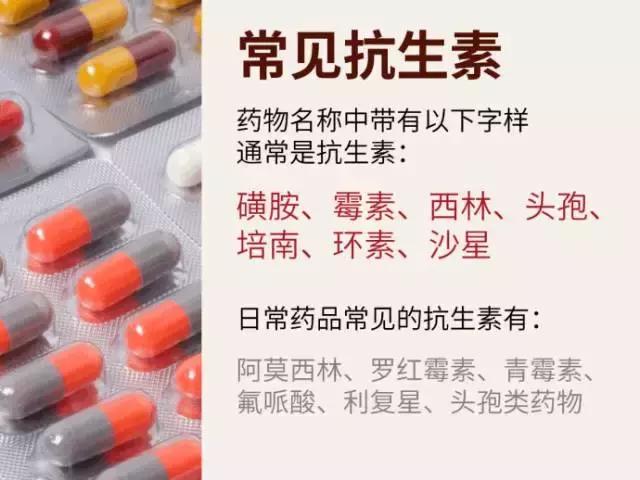

哪些属于抗生素?

什么情况下一般不使用抗生素?

1、感冒。由于90%的感冒都是由于病毒引起的,所以抗生素起不到治疗作用,即使是病毒+细菌引起的感冒,医生给你开了抗生素吃,下一次还出现相同症状时,这次的抗生素也可能起不到作用了。

2、慢性咽炎。慢性咽炎一般没有病菌,不推荐抗生素。

3、妇科炎症。只有急性炎症发作才可能使用抗生素,而且必须是医院进行过细菌培养和药敏试验后选用的药物。一般的慢性盆腔炎、慢性子宫颈炎不需要抗生素。

4、前列腺炎。只有约5%—10%的前列腺炎是明确的细菌感染,需要使用抗生素,请不要觉得自己有炎症不舒服擅自使用抗生素!

5、非感染性腹泻。由于病毒引起的寒湿型腹泻、暴饮暴食引起的伤食型腹泻、以及脾虚腹泻,都不推荐用抗生素。

6、腮腺炎。腮腺炎好发于青少年,它是由于病毒入侵引起炎症,所以一般抗生素无效。

7、鼻窦炎。鼻窦炎可能由细菌或病毒引起,患者无法判断时应遵循医生的意见选择用药。

8、胃炎。有些胃炎是细菌性感染,比如幽门螺杆菌,但这种病菌比较顽固,它并不能靠一般的抗生素清除。至于由于自身饮食习惯不好导致的胃炎,抗生素更无法起到效果。请在医生指示下选择用药。